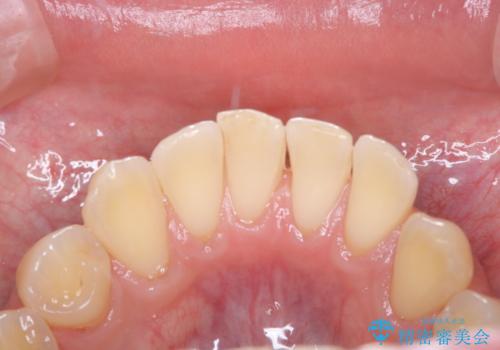

- 数年ぶりに歯科へ来院とのこと。全体的に歯のクリーニングをしてほしいとのことでした。

PMTC60分コースを行いました。